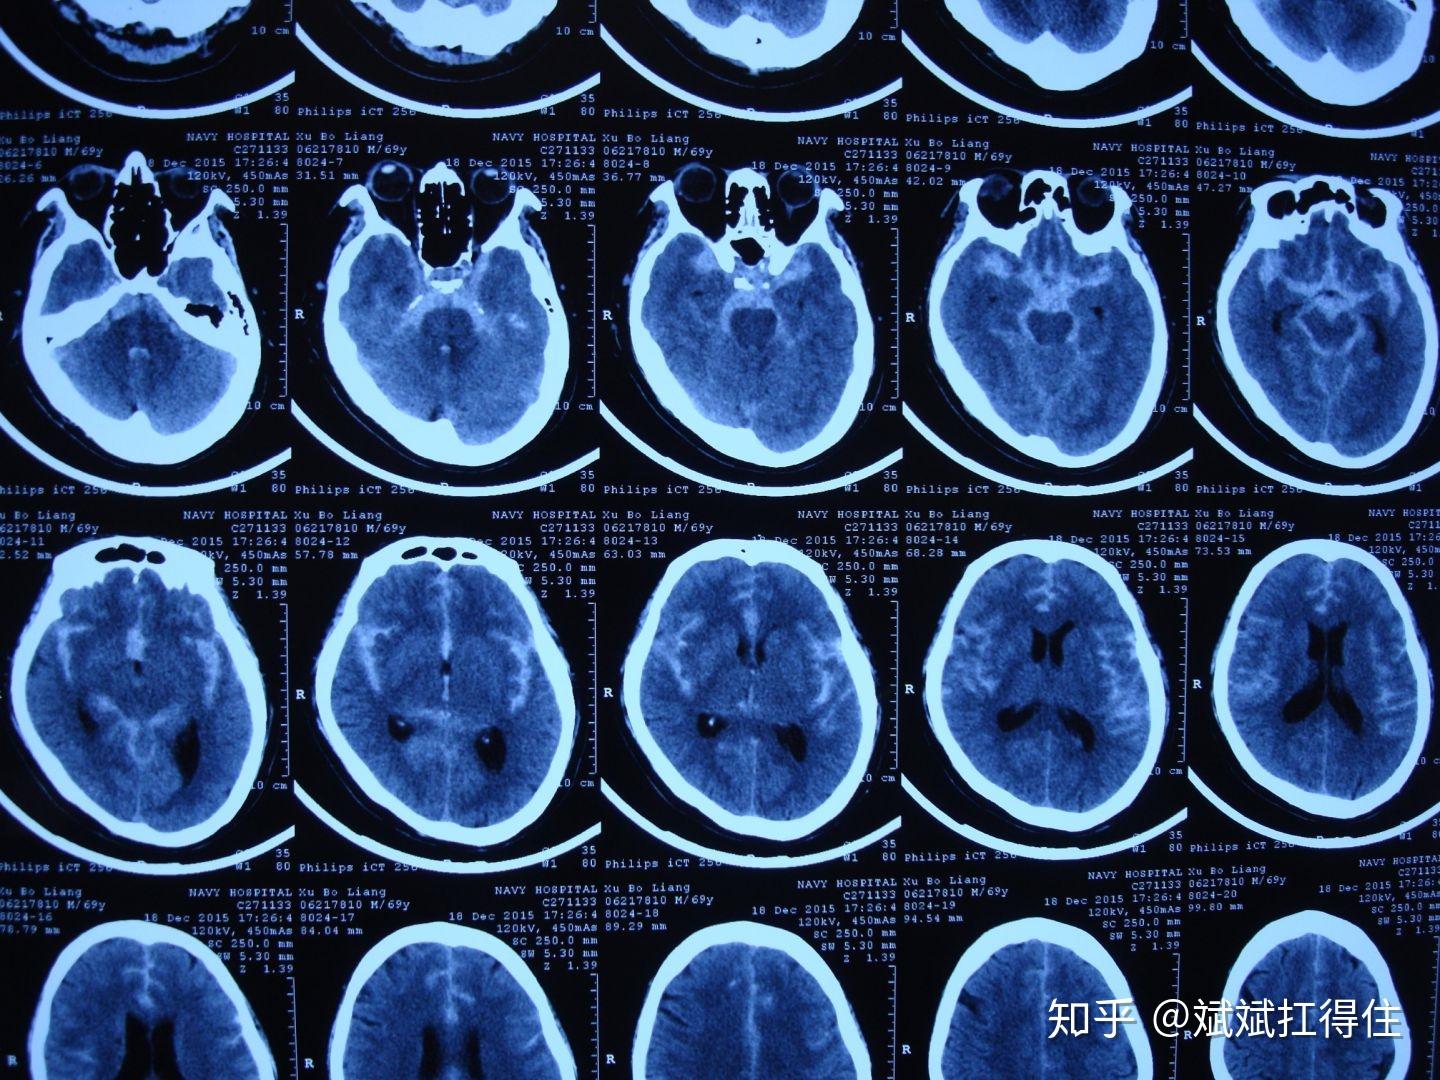

图1:蛛网膜下腔的ct表现图2:cta提示前交通动脉的动脉瘤图3:血管造影